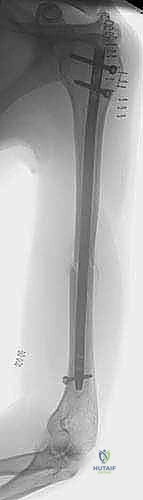

* الشكل القمعي المتغير: الثلثان العلويان من قناة العضد يتميزان بشكل أسطواني وواسع نسبياً، لكن القناة تتضيق بشكل حاد وسريع في الثلث السفلي لتصبح صلبة جداً. هذا التباين الهندسي يجعل تحقيق "التثبيت التداخلي" (Interference fit) - أي أن يثبت المسمار نفسه بمجرد حشره في العظم - أمراً شبه مستحيل. لذلك، أصبح استخدام "البراغي القابلة للقفل" (Locking Screws) في أعلى وأسفل المسمار هو المعيار الذهبي العالمي الذي يطبقه الأستاذ الدكتور محمد هطيف لضمان عدم دوران العظم أو تحركه بعد الجراحة.

التثبيت بالمسمار النخاعي الأمامي: المعيار الذهبي الحديث

يُعد "المسمار النخاعي الأمامي" (Antegrade Nailing) - أي الذي يتم إدخاله من جهة الكتف نزولاً نحو الكوع - قمة التطور في علاج كسور منتصف وأعلى عظم العضد. تعتمد هذه التقنية على مبدأ "التثبيت البيولوجي" (Biological Osteosynthesis). بدلاً من فتح الذراع بالكامل لترتيب قطع العظم بدقة هندسية (مما يقتل التروية الدموية)، يتم إدخال سيخ معدني قوي (مصنوع من التيتانيوم المتوافق حيوياً) داخل تجويف العظم ليعمل كدعامة داخلية، مع ترك الكسر المفتت في بيئته الدموية الطبيعية الغنية بالخلايا الجذعية لتلتئم بسرعة.

4. فتح القناة وتوسيعها (Reaming):

باستخدام سلك توجيهي دقيق (Guide Wire) وتحت مراقبة الأشعة المباشرة، يتم تمرير السلك عبر الكسر وصولاً إلى نهاية العظم فوق الكوع. بعد ذلك، يتم استخدام موسعات مرنة (Flexible Reamers) لتوسيع القناة النخاعية قليلاً. هذا التوسيع لا يهيئ مكاناً للمسمار فحسب، بل يدفع أيضاً "نشارة العظم" الغنية بالخلايا البانية للعظم إلى منطقة الكسر، مما يعمل كطُعم عظمي ذاتي (Autograft) يسرع الشفاء.

5. إدخال المسمار النخاعي (Nail Insertion):

يتم اختيار مسمار التيتانيوم بالطول والقطر المناسبين اللذين تم قياسهما مسبقاً، ويتم إدخاله بلطف فوق سلك التوجيه حتى يعبر منطقة الكسر ويستقر في مكانه المثالي.

6. القفل الديناميكي والاستاتيكي (Locking):

لمنع المسمار من الدوران أو الانزلاق، يجب تثبيته ببراغي عرضية. يتم إدخال البراغي العلوية في الكتف عبر جهاز توجيه متصل بالمسمار. أما البراغي السفلية (فوق الكوع)، فتتطلب مهارة فائقة؛ حيث يتم إدخالها عبر شقوق صغيرة جداً (1 سم) باستخدام تقنية "اليد الحرة" (Freehand Technique) تحت توجيه الأشعة، مع حماية العصب الكعبري والأوعية الدموية بدقة.